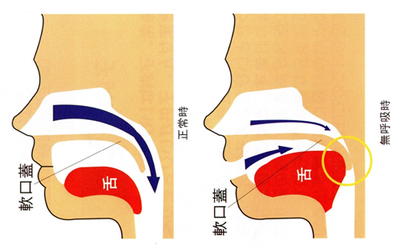

特に下顎は舌の収納場所であるため、下顎の歯列弓が縮小すると舌が奥に引き込まれて下の右の図にあるように、無呼吸を起こしやすくなる形態を作ってしまいます。

左:正常の舌の位置 右:無呼吸時の舌の位置